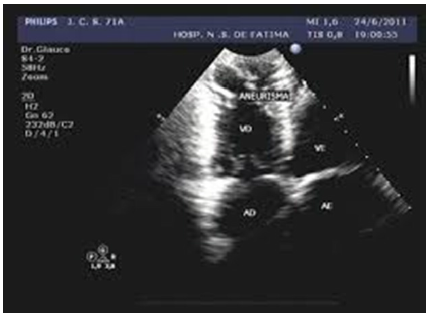

Paciente, 34 anos, portador de insuficiência

renal crônica, evoluiu com quadro de

hipotensão arterial, agitação e taquicardia.

O cardiologista clínico, após avaliar os

níveis altíssimos de ureia, fez sua hipótese

diagnóstica e solicitou um ecocardiograma

à beira do leito. Em relação ao caso clínico,

assinale a alternativa correta.